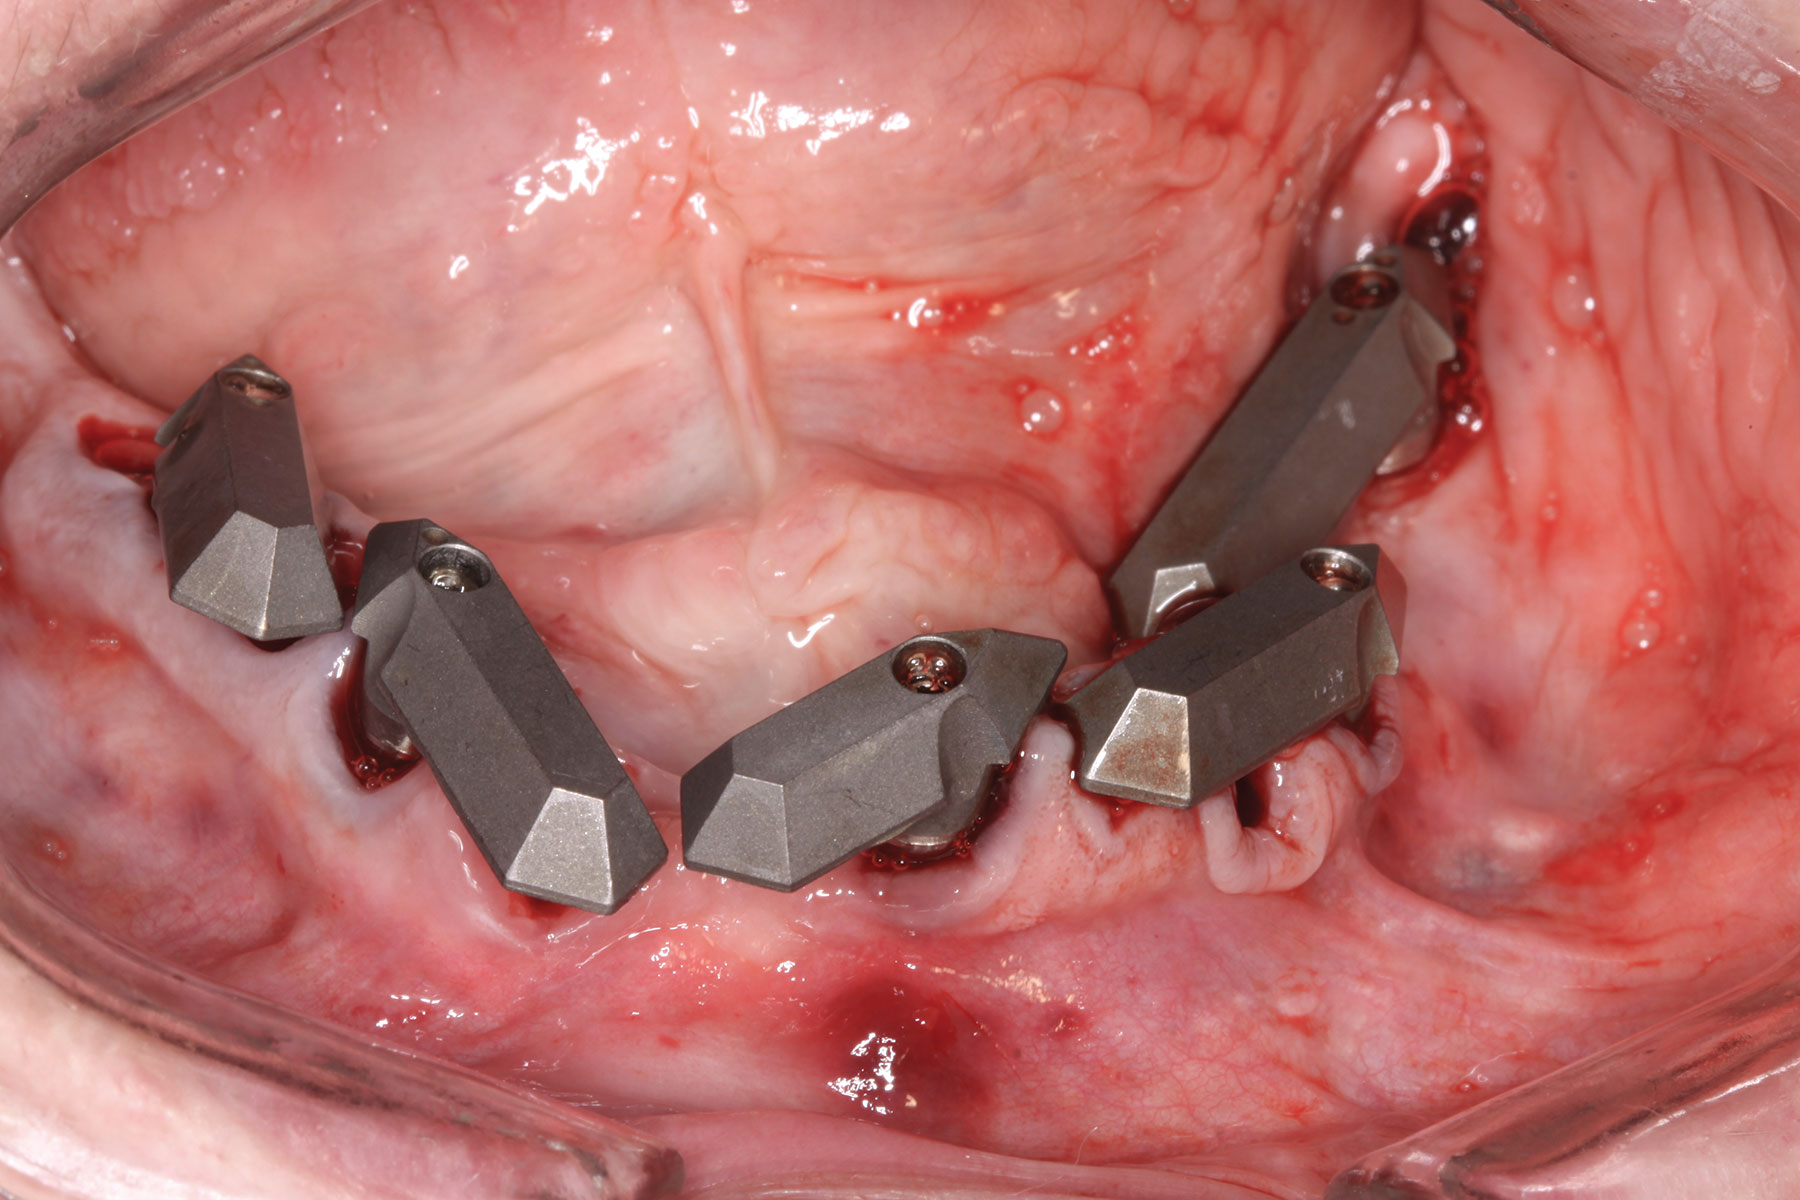

A week later the patient presented for surgery for extraction and replacement of her existing maxillary dentition with implants and a screw-retained provisional implant restoration. Teeth Nos. 2, 4, and 6 through 11, 13, and 14 were carefully extracted with attention paid to retaining site dimensions. Immediate implants were inserted into sites Nos. 4, 6, 8, 11, and 13 with high insertion torques in excess of

40 Ncm. Subsequently, multi-unit abutments were placed on all the implants and torqued to 30 Ncm, and scan gauges were placed on implant Nos. 8 and 11 (Figure 12 and Figure 13).

Fig 12. Partial extractions and placement of implants and multi-unit abutments.

Figure 12

Fig 13. Initial scan of scan gauges with residual teeth retained for reference.

Figure 13